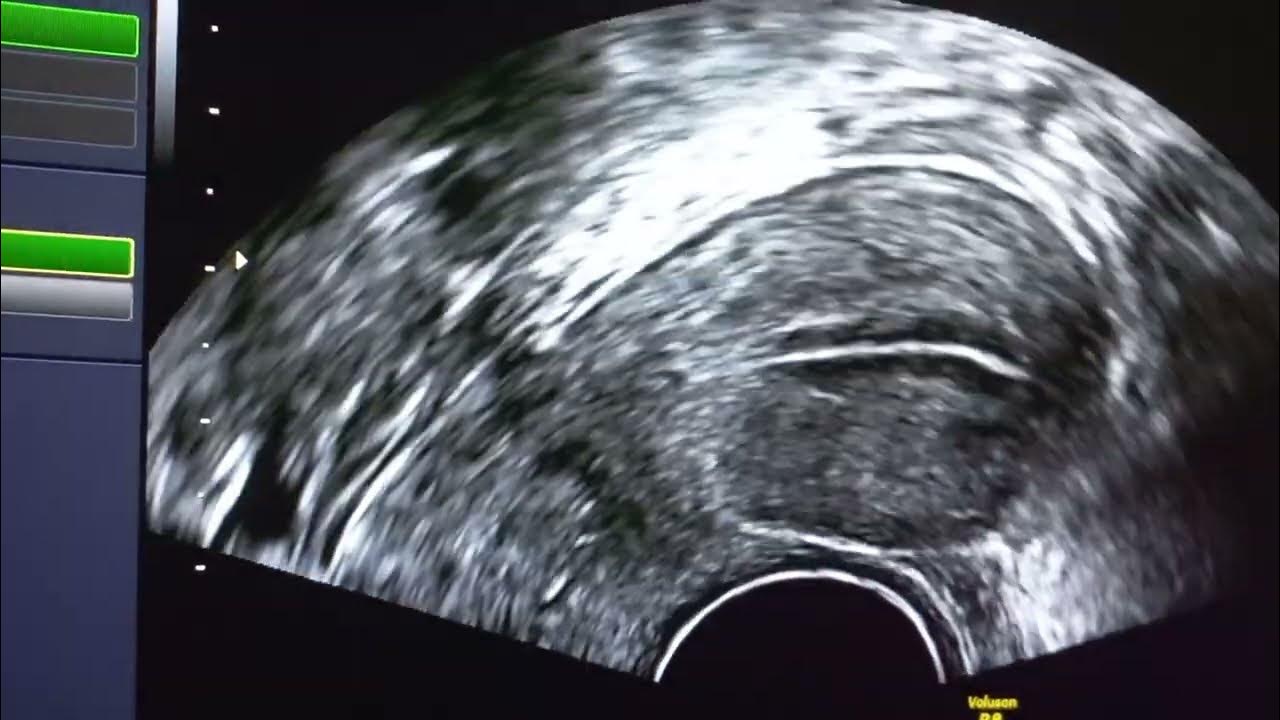

From www.youtube.com

iui success in first attempt. eggs, and uterus ultrasound. iui with rfsh hmg dual trigger YouTube How Many Eggs Are Needed For Iui Intrauterine insemination (iui) can increase their likelihood of becoming pregnant. The former involves taking fertility drugs so that more than one follicle (typically two or three) matures and improves. The procedure involves collecting sperm and inserting it into the. Between days 3 through 5 of your menstrual cycle, many women will take medications to stimulate your ovaries to grow. A. How Many Eggs Are Needed For Iui.